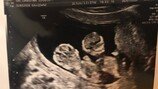

김재우는 21일 자신의 SNS에 “저희가 노력하긴 했지만 여러분들이 주신 선물같아 태명은 ‘강황이’이라고 지었어요. 15주 되었습니다”라고 아내의 임신 사실을 전했다.